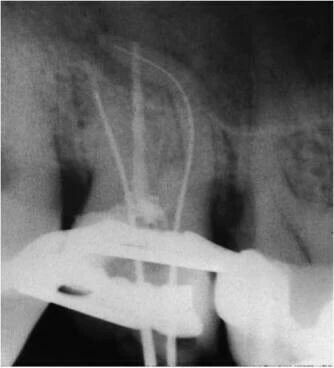

Trên phim X-quang ban đầu:

- (a) cho thấy một cây trâm số 15 góc cong 35 độ. Hình X-quang sau khi sửa soạn ống tủy

- (b) với cây trâm số 40 góc cong 13o.

Kết quả của việc sửa soạn ống tủy đã làm cho ống tủy bị chuyển dịch so với ban đầu. Có hiện tượng giảm chiều dài làm việc. Bạn có thấy rằng ống tủy đã bị làm thẳng hơn?

Trong hình minh họa bên dưới (a) là hình ảnh ống tủy bị làm thẳng và thủng thành; (b) Sự tạo khấc tại vị trí bắt đầu của đoạn cong và mất chiều dài làm việc.